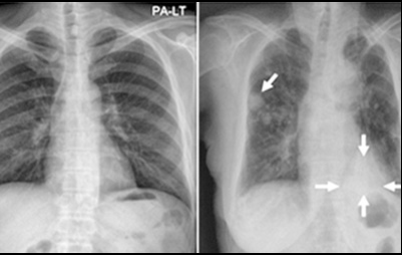

10. 폐암 초기 증상 - 상대 정맥 증후군

상대정맥 주위에 폐암이 생겨 상대정맥을 압박할 때 생기는 증상을 말합니다 . 혈액 순환 장애가 생겨 머리와 팔이 심하게 부어 오르고 호흡 곤란 , 가슴 정맥 돌출 등의 증상이 발생할 수 있습니다 .